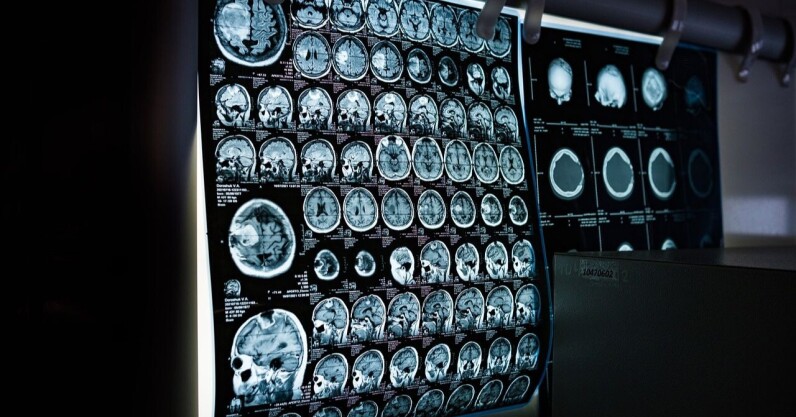

A new VR system that uses eye-tracking technology can calm children while they undergo Magnetic Resonance Imaging (MRI) scanning. Developed by researchers at King’s College London, the method aims to mitigate children’s tendency to move during MRI scans. by engaging them in immersive virtual reality experiences. Compared to adults, children are less likely to remain still inside the scanner, often negatively influenced by the large size of the machine and the loud noises. As movement can disrupt the quality of the images, doctors frequently have to resort to approaches such as sedation or general anaesthesia. To address this, the researchers have…